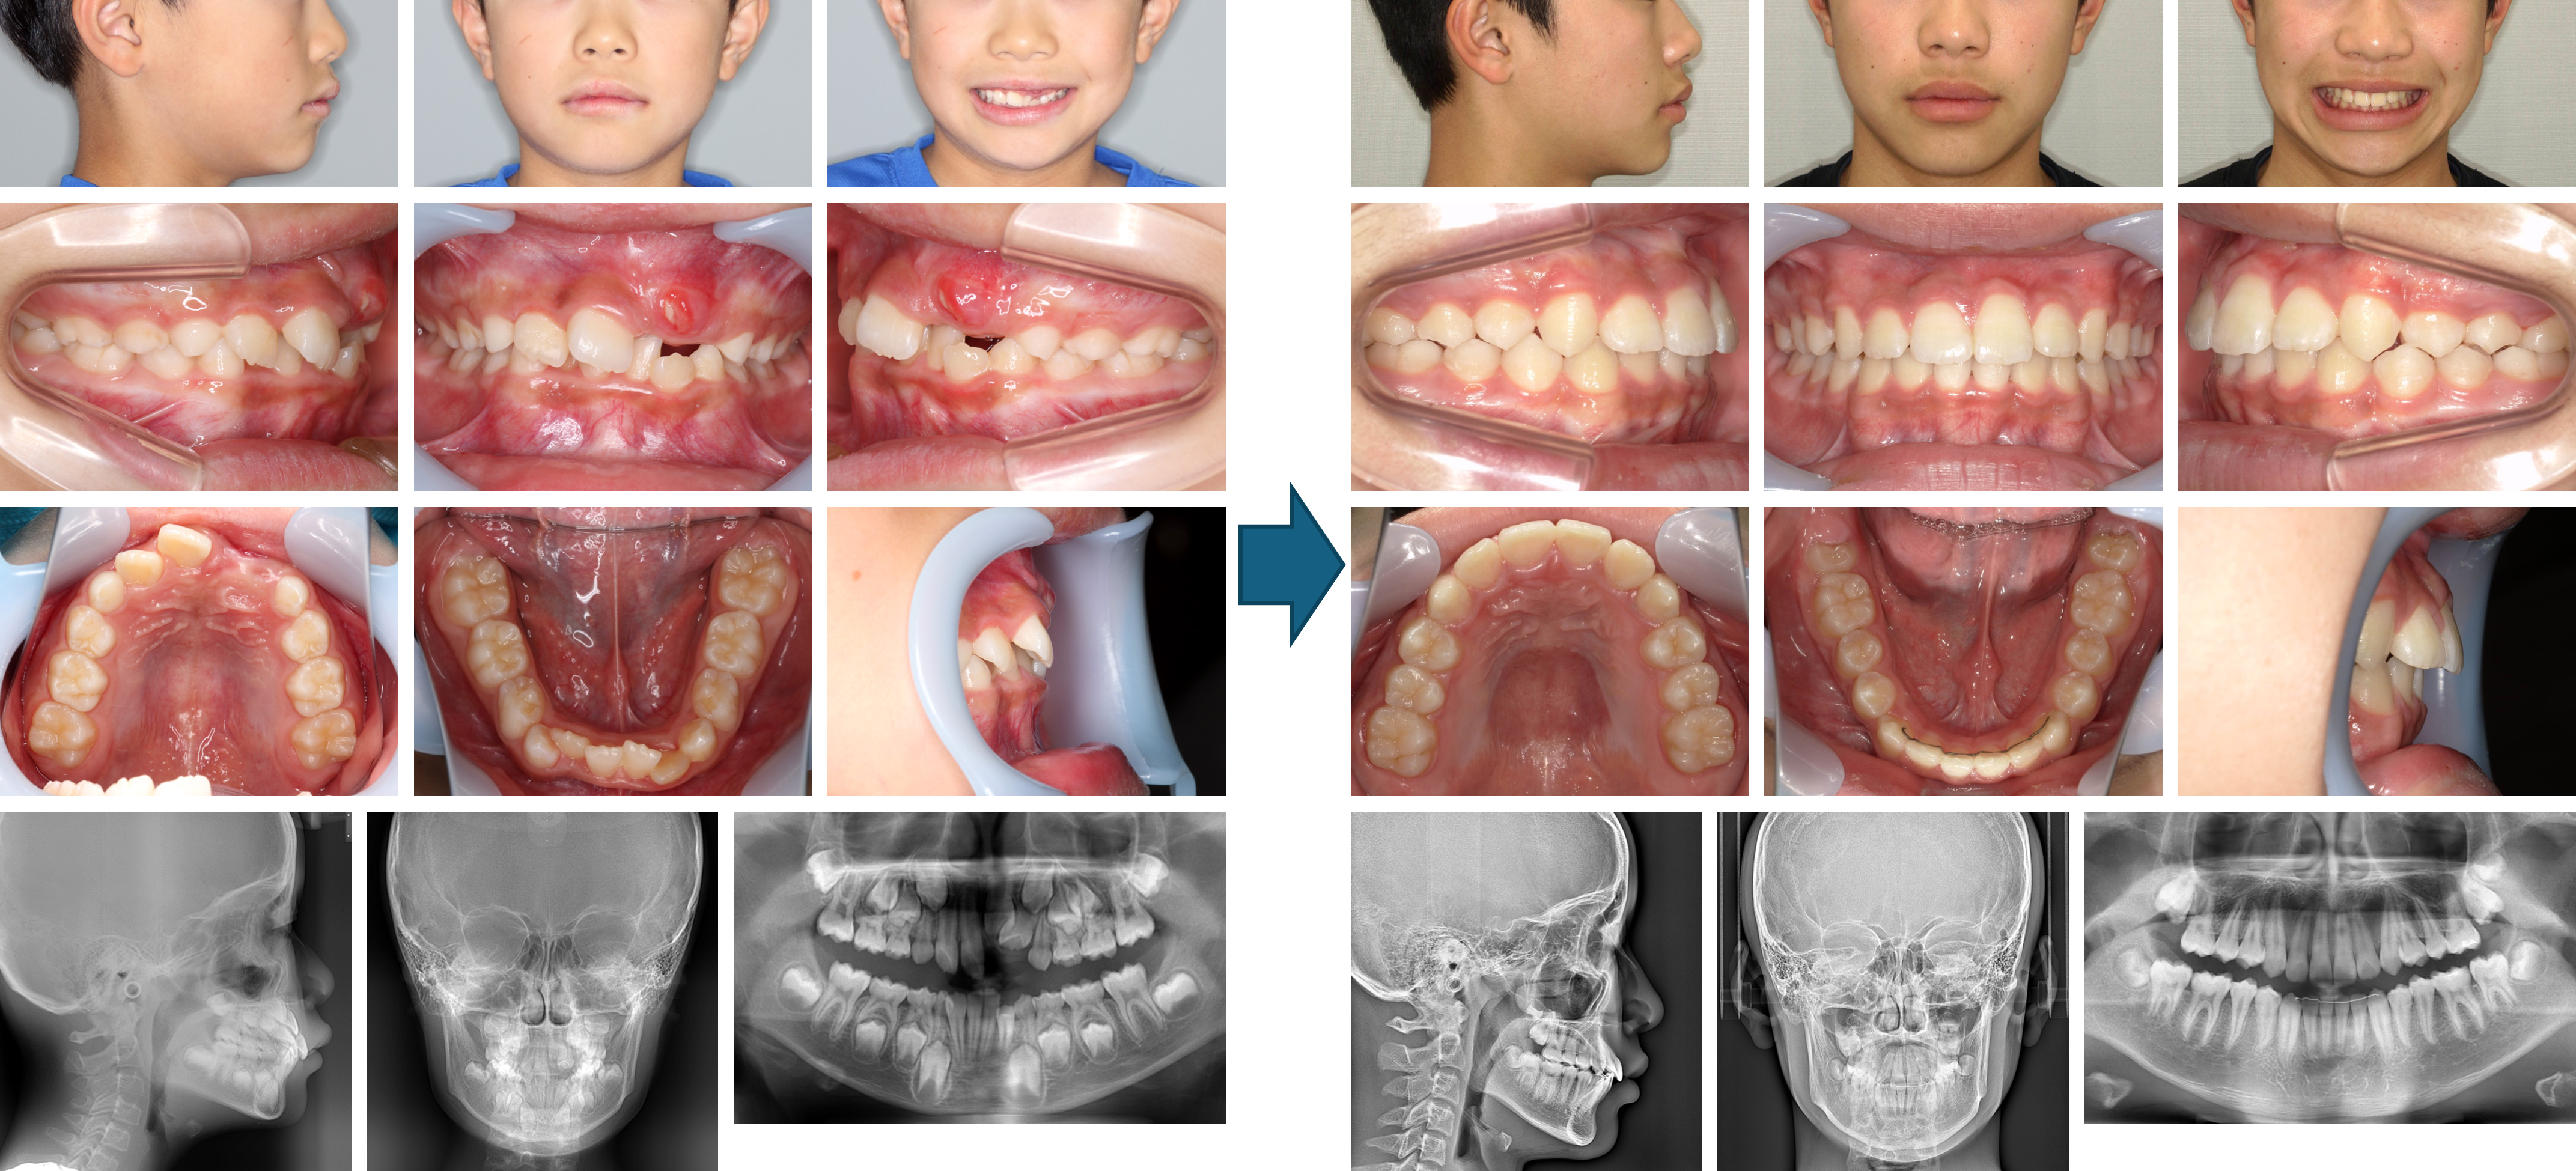

【治療例 K7719】初診時年齢:12歳1か月 / 性別:男性 / 主訴:出っ歯で口が閉じにくい

症例の概要:主訴は出っ歯で口が閉じにくい。サービカルヘッドギアと2×4装置にて上顎骨の成長抑制、下顎の成長促進を行った。さらにマルチブラケット装置にて緊密な咬合を獲得し、好ましい側貌を得ることが出来た。

主訴: 出っ歯で口が閉じにくい

診断名: 上顎前歯が唇側傾斜した上顎前突症例

使用した主な装置: マルチブラケット装置、サービカルヘットギア、歯肉切除

抜歯/非抜歯および抜歯部位: 非抜歯

※こちらの症例は2020年11月から2023年4月に行った矯正治療です(現在も経過観察中)

治療期間:2年5か月

治療回数:25回